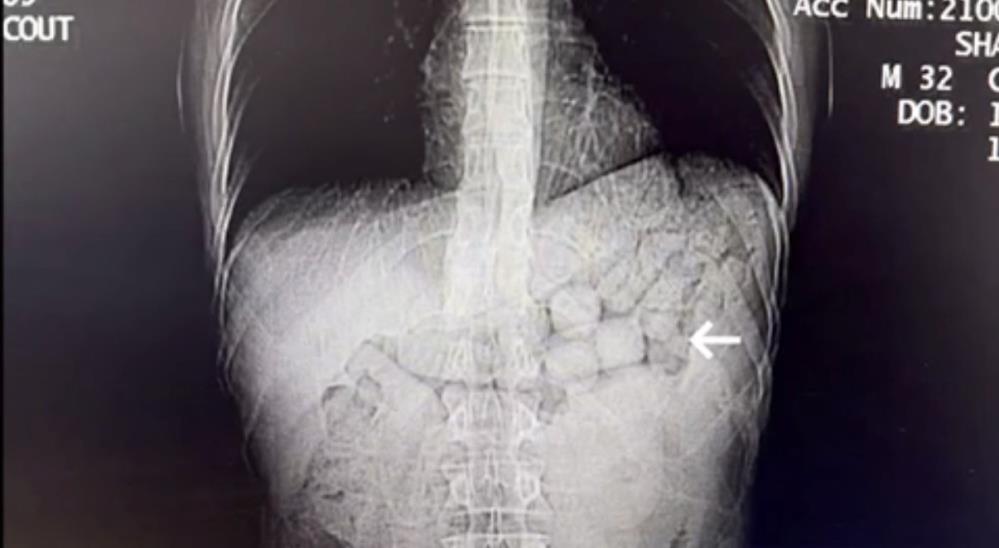

Hastanede çekilen tomografi görüntülerinde şüphelilerin mide ve bağırsak bölgelerinde yabancı cisimlere rastlandı.

Yaklaşık 3 gün süren kontrollerin ardından, şahıslardan 91 kapsül halinde toplam 807,15 gram metamfetamin maddesi ele geçirildi.